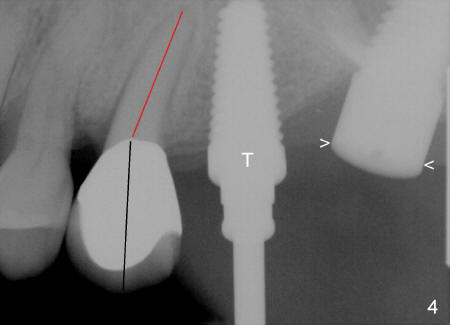

The final tap 6x17 seems to be parallel to the long axis of the crown of the neighboring tooth (Fig4: black line). At that time it was not realized that the long axis of the root (red line) matters the most. It is not the same as that of the crown! The implant at the site of #15 does not give us any guidance since small portion of it is exposed (below arrowheads).